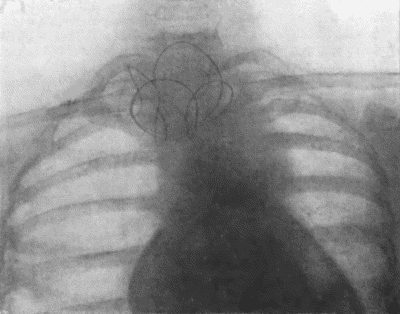

304 73.Radiogram of Innominate Aneurysm after Treatment by Moore-Corradi method

309 74.Thoracic Aneurysm threatening to rupture